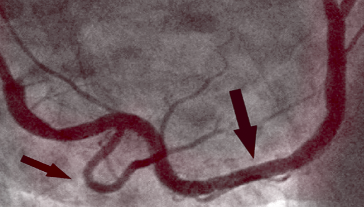

PO KÚRE

Na fotografii vpravo vidíme vyčistenú pravú koronárnu tepnu bez stôp kalcifikovaného aterosklerotického plátu u toho istého pacienta po 1 mesiaci kúry. Neexistujú žiadne smrteľné usadeniny cholesterolu. Krv voľne prúdi a okysličuje všetky orgány.